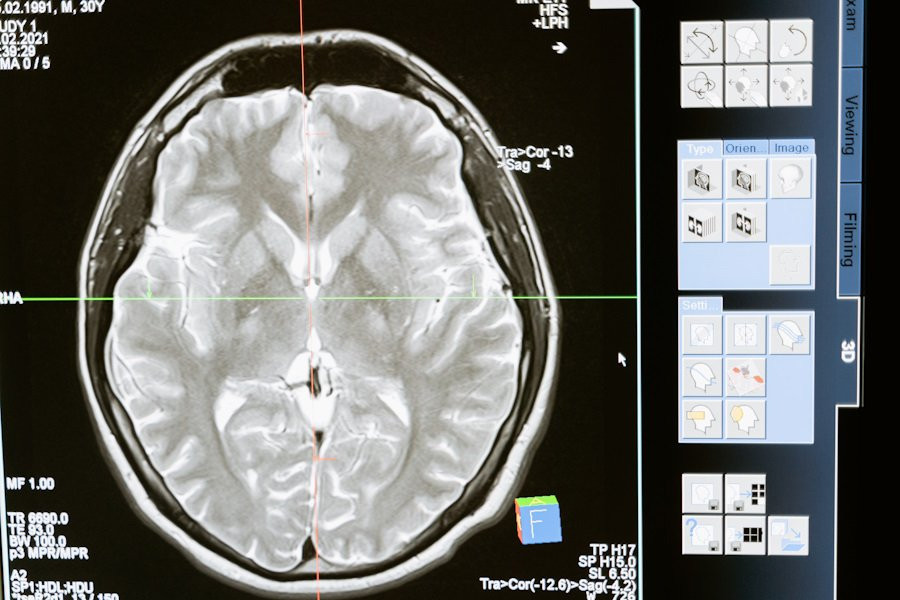

Воспользовавшись функциональной МРТ (фМРТ), специалисты определили конкретную область мозга, отвечающую за руминацию, — это дорсально-медиальная префронтальная кора (ДМПК).

Исследование показало, что ДМПК взаимодействует с другими частями мозга, особенно с левой нижней лобной извилиной и правым височно-теменным соединением. Данная связь играют немаловажную роль в понимании процесса руминации, поскольку эти области мозга связаны с речью и оценкой социальных ситуаций.

Учёные отмечают, что руминация представляет собой одну из наиболее важных моделей мышления, и их исследование показывает, что склонность к ней может быть связана с определенными связями в мозгу, которые можно измерить с помощью фМРТ. Они планируют использовать нейровизуализацю для отслеживания и управления психическим здоровьем.